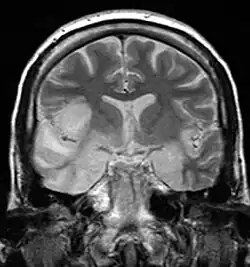

| MRI scan image shows high signal in the temporal lobes and right inferior frontal gyrus in someone with herpes simplex encephalitis. | |

Limbic encephalitis refers to inflammatory disease confined to the limbic system of the brain. The clinical presentation often includes disorientation, disinhibition, memory loss, seizures, and behavioral anomalies. MRI imaging reveals T2 hyperintensity in the structures of the medial temporal lobes, and in some cases, other limbic structures. Some cases of limbic encephalitis are of autoimmune origin.[9]

- Brain scan, done by MRI, can determine inflammation and differentiate from other possible causes.